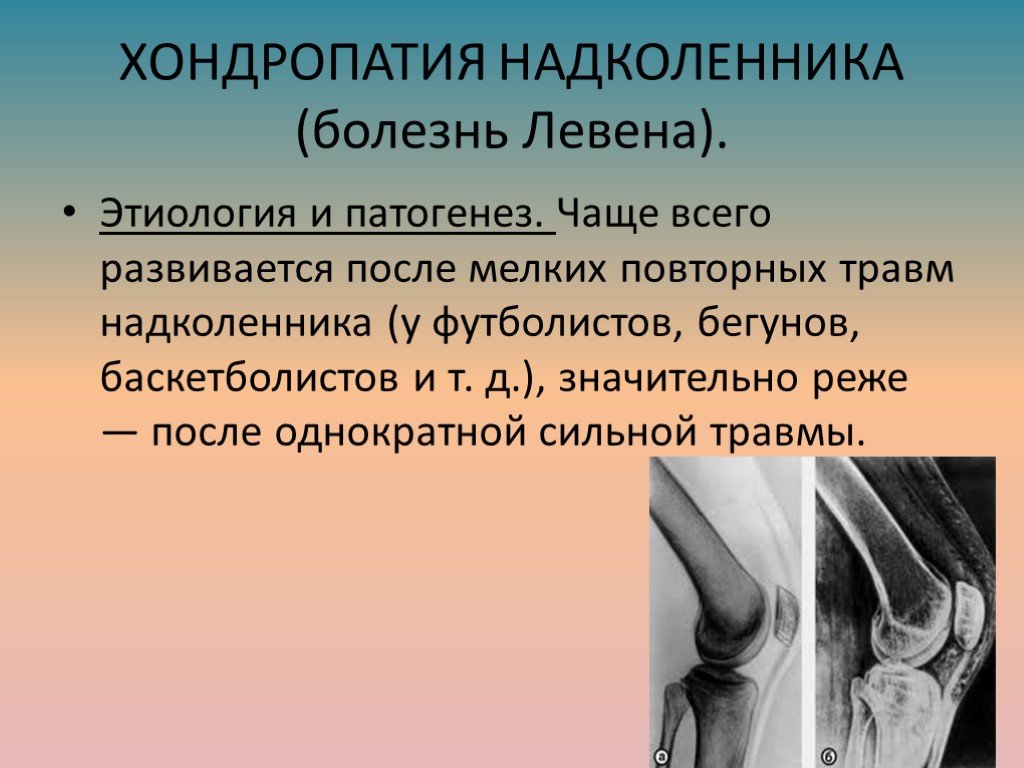

Ларсена йохансона

Ларсена йохансона 146 фото